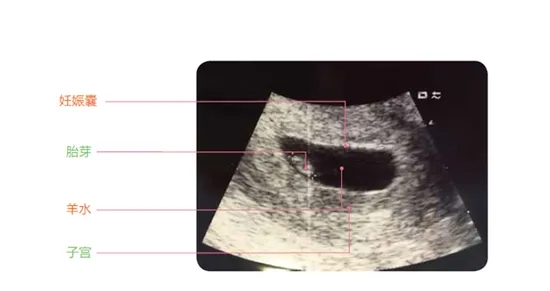

2.、B超檢查

當(dāng)然,除了驗血,也有的醫(yī)生可能會讓做B超檢查,但也可能因為天數(shù)太少,醫(yī)生會給開陰超檢查,相比來說,陰超要比腹部B超看的更清楚些。

這個階段,醫(yī)生會重點看 孕囊(一般是在孕30-40天孕囊出現(xiàn)),醫(yī)生會根據(jù)“孕囊的大小、位置、性狀”等,來判斷胚胎是否在正常發(fā)育。

① 孕囊大小

這里說的“孕囊大小”,指的是孕囊的直徑,在懷孕6周時孕囊的直徑約為2cm。

② 孕囊形狀和位置

不少人,在懷孕早期會根據(jù)孕囊的性狀來判斷懷的男孩還是女孩,其實這是沒科學(xué)道理的,不過在這個階段,的確可以通過B超看孕囊的性狀是“橢圓形還是圓形”,而醫(yī)生會根據(jù)孕囊的性狀、位置等判斷胎兒的發(fā)育情況。